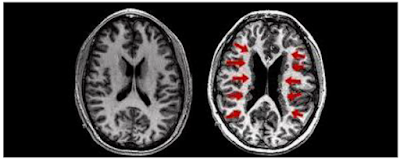

Hingga saat ini para ahli neurologis belum dapat mengetahui fungsi otak manusia secara keseluruhan, baru beberapa bagian saja yang sudah dapat dikenali fungsinya secara pasti dan memiliki keterkaitan satu sama lain. Pada saat manusia melakukan kegiatan pemprosesan bahasa, aktivitas pada himesfera bagian kiri akan tampak lebih besar daripada hemisfera bagian kanan, sedangkan pada orang yang mengalami gangguan disleksia aktivitas himesfera kedua bagian menjadi sama besar (Devaraj, 2006:35).

| Perbandingan Isyarat Saraf antara otak normal dengan otak penderita disleksia |

Salah satu penyebab terhambatnya anak disleksia dalam melakukan pemprosesan bahasa adalah dikarenakan terjadinya pemusatan pada perjalanan saraf penghubung atau confusing traffic jam of nerve signal menjadikan proses penginformasian antar saraf semakin lama (Devaraj, 2006:36). Berikut adalah hasil scanning FMRI (Functional Magnetic Resonance Imaging) anak disleksia pada saat melakukan pemprosesan kegiatan membaca.